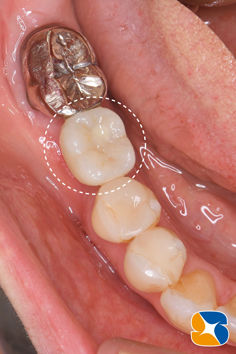

後日ブリッジを外してみると、ブリッジの土台の歯根が見事に粉々に砕けていました。